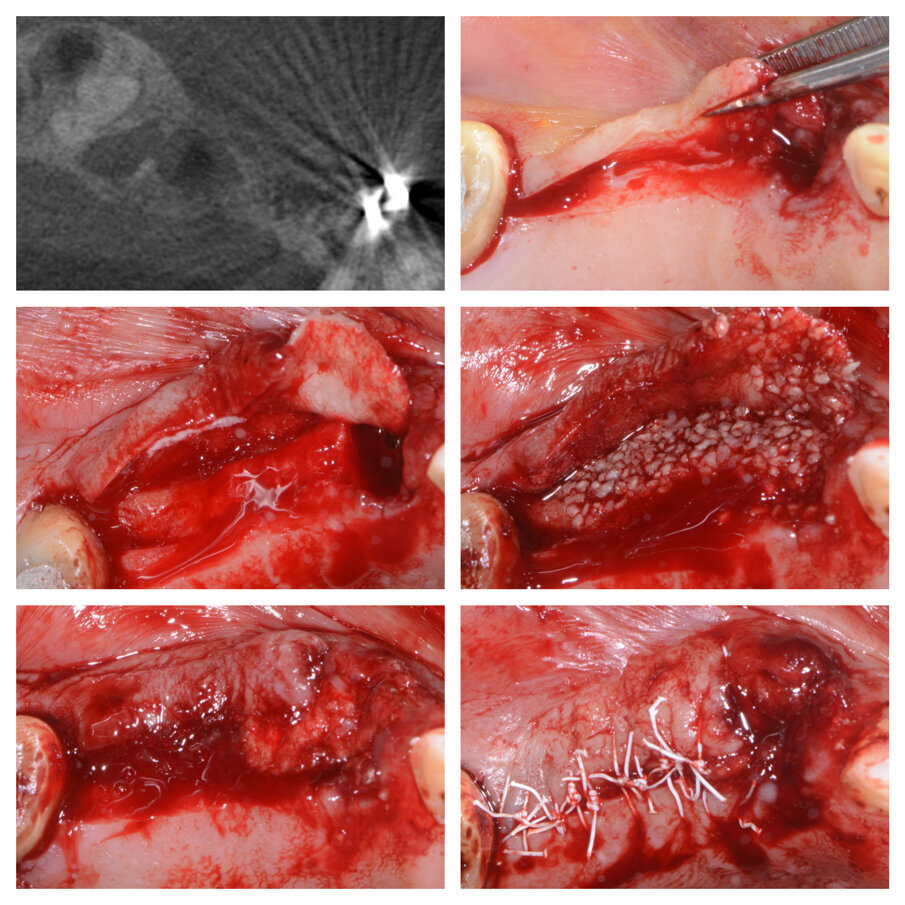

Fig. 4a_Elemento 36 mesio inclinato, deficit orizzontale in zona 35 risolto con tecnica S.A.T.

Fig. 6a_Perdita di elemento di ponte 24 e deficit in zona 25, fasi chirurgiche e guarigione.

La tecnica è indicata per elementi dentali da estrarre mesio inclinati o elementi di ponte, che presentino un deficit orizzontale della cresta ossea a fianco dell’elemento da estrarre. Il protocollo operativo prevede, dopo l’estrazione, una incisione in cresta fino al dente contiguo e intrasulculare per mezzo dente sia vestibolare che buccale-palatale, se necessario. Si procede poi scollando ed evidenziando la parte ossea dove dovremo posizionare la membrana e il biomateriale, senza eccedere poiché lo scollamento minimo ci garantirà la stabilità dell’innesto. Raggiunte le pareti che riprendono uno spessore osseo morfologicamente normale si interrompe lo scollamento e si imbusta una membrana in collagene precedentemente tagliata e bagnata con la colla di fibrina, in modo che si incolli al lembo vestibolare. A questo punto il biomaterale miscelato con la colla di fibrina (Sticky Bone) viene imbustato poco per volta iniziando dall’alveolo e poi all’interno del sito creato dallo scollamento, senza necessità di fori nella corticale (Figg. 2a, 3a, 4a, 5, 6a). La rigenerazione viene guidata dai tessuti che ci indicheranno quanto materiale poter inserire, non effettuando scarichi verticali è il lembo stesso a essere contenitivo e a dare stabilità all’innesto. Il lembo viene suturato a punti staccati singoli ottenendo una chiusura per prima intenzione senza dover incidere il periostio (Figg. 1a, 2a, 3a, 6a); mentre nella zona dell’alveolo, in cui gli strati di membrana possono essere aumentati, la sutura sarà incrociata e la guarigione per seconda intenzione. Ovviamente se dovessimo trovarci in difficoltà potremo creare un rilascio periostale, ponendo sempre attenzione a non far venire meno quella capacità contenitiva del lembo che è alla base di questa tecnica. Nei casi presentati il rilascio periostale non è stato eseguito, iniziare il lembo con un incisione bisellata in cresta può essere d’aiuto a evitare il rilascio periostale (Fig. 2a).

La tecnica che viene presentata è assolutamente mini invasiva in quanto permette una ricostruzione della cresta orizzontale contestuale all’alveolo senza dover prelevare osso dal paziente, senza incisioni di scarico e senza dover forare la corticale già presente. La tecnica chirurgica è stata eseguita utilizzando idrossiapatite bovina con il 30% di atelocollagene (Hypro-Oss® Bioimplon) ed idrossiapatite bovina pura (Bio-Oss® Geistlich Pharma) bagnati con colla di fibrina umana (Tisseel® Baxter ed Evicell® Johnson & Johnson) per rendere il materiale più maneggevole ed appiccicoso rispetto ai semplici granuli, e membrane in collagene riassorbibile (Hypro-Sorb M® Bioimplon e Bio-Gide® Geistlich Pharma).